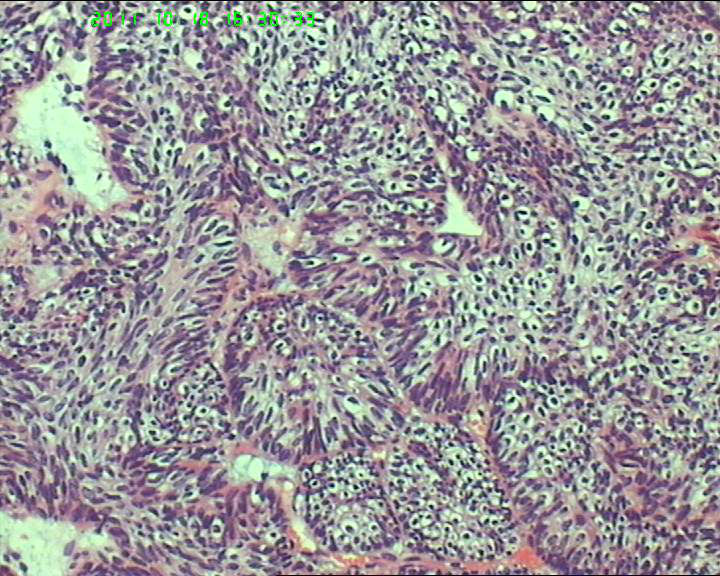

70岁女性体检发现膀胱肿物,是癌吗?

膀胱后壁一2*1cm大小肿物